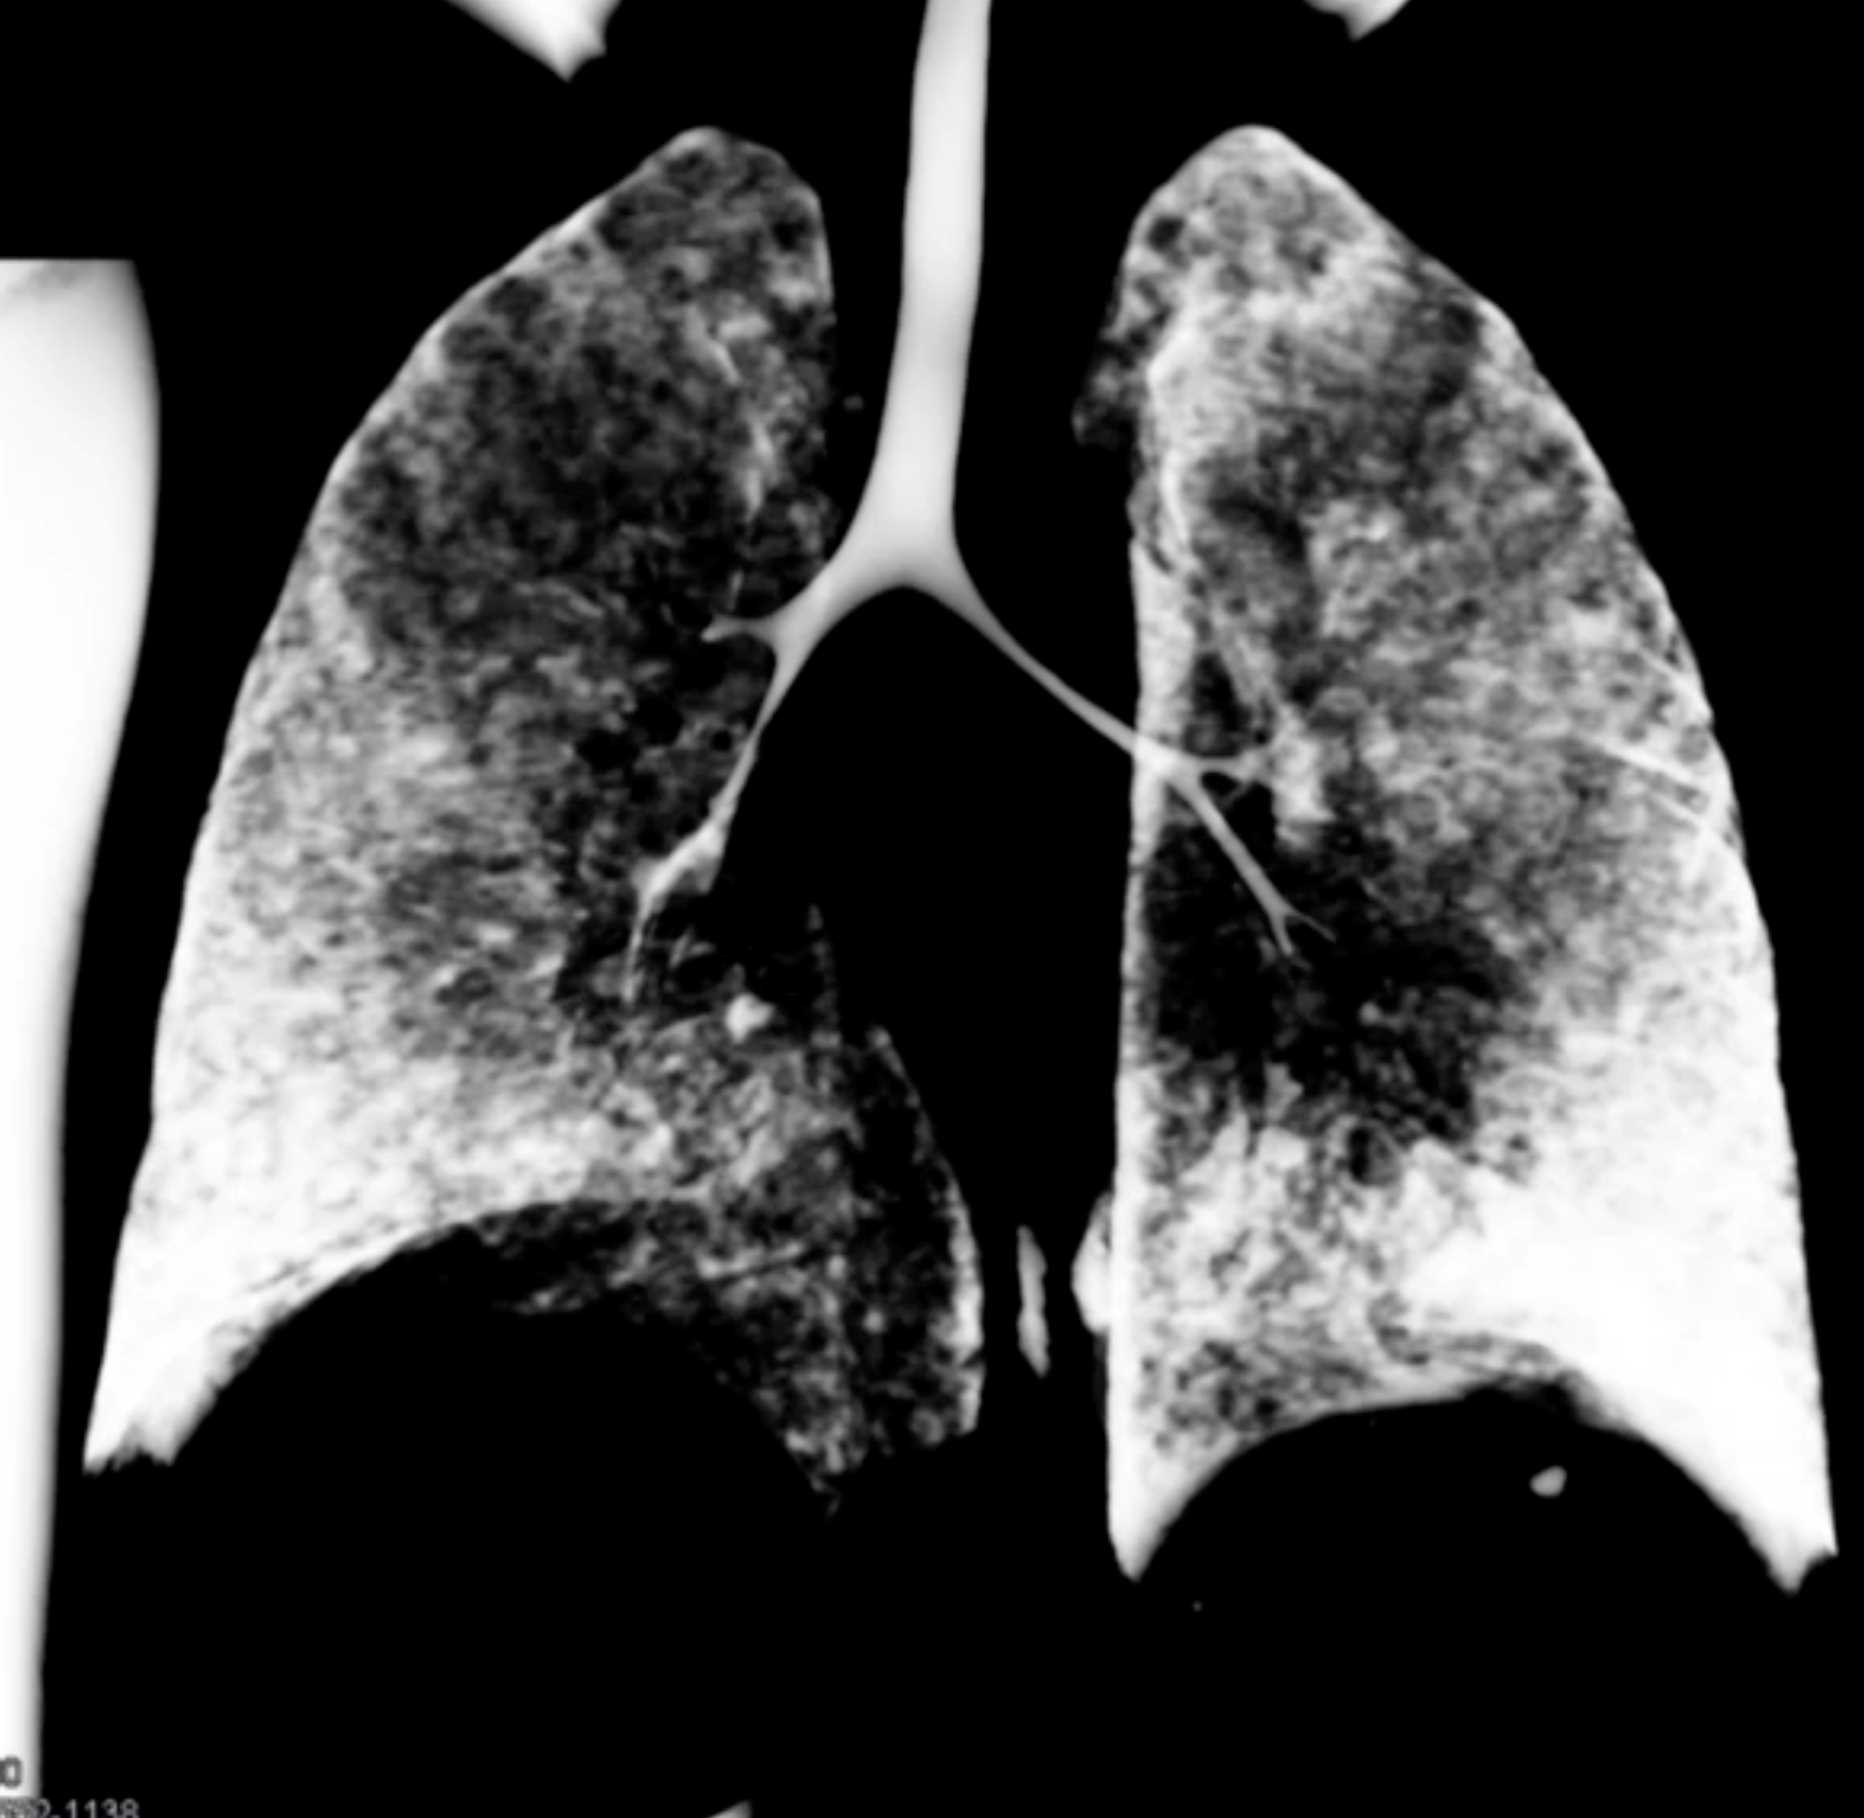

Histoplasmosis and Normal Thymus